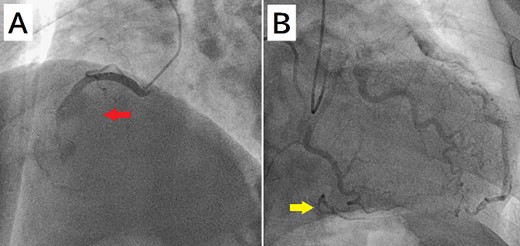

A 52-year-old man with transient ischemic attack was transferred to our hospital. He had a history of hypertension and dyslipidemia. He was conscious and had no particular symptoms after arriving at our hospital; however, an electrocardiogram showed ST-segment elevation in leads II, III, aVF, and V1–4. Enhanced computed tomography revealed a giant CAA at the RCA (Fig. 1). The aneurysm measured 50 mm in diameter and was completely occluded by a thrombus. Additionally, the coronary artery distal from the CAA did not show contrast. Emergency coronary angiography was performed. The RCA was occluded at segment #2 proximal to the CAA, and the CAA did not show contrast (Fig. 2A); however, the artery distal to the CAA showed contrast via a collateral artery from the left circumflex artery (Fig. 2B). Anticoagulation therapy involving intravenous heparin was started. After several hours, the ST-segment elevation disappeared quickly, and there were no particular symptoms. The creatine kinase level spiked to a maximum of 1475 IU/L, which then decreased to 432 IU/L on the next day. Four days after starting therapy, enhanced computed tomography and coronary angiography were performed again. They showed slight contrast in the CAA and the distal coronary artery (Fig. 3). Thus, surgery was performed to prevent the CAA from rupturing.

Enhanced computed tomography shows a giant coronary artery aneurysm (arrow) at the right coronary artery, which is occluded completely by a thrombus.